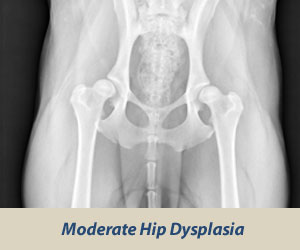

Choroba je spôsobená nedostatočným vývinom kĺbovej jamky a bedrového kĺbu. Nerovnomerný rast kostí spôsobí poškodenie chrupavkovitých častí. Zmeny na bedrových kĺboch je možno dobre pozorovať na RTG snímkach. DBK postihuje najčastejšie veľké a obrie plemená, môže sa však vyskytovať u ktoréhokoľvek plemena.

Diagnostika DBK

Diagnostikuje sa pomocou RTG snímku. Zoznam certifikovaných posudzovateľov DBK, DLK, pre vyhotovenie kvalitných snímkov. Snímok musí byť kvalitný a označený tak, aby nemohol byť zamenený. Snímok sa zasiela klubom určenému veterinárnemu lekárovi, ktorý vyhodnocuje snímky v rámci SR.

RTG snímok DBK

Pes leží na chrbte s natiahnutými panvovými a hrudníkovými končatinami tak, aby telo psa tvorilo os. Panvové končatiny sa ťahajú rovnobežne smerom dozadu. Pri RTG DBK je pes v narkóze, aby bolo zabezpečené dostatočné uvoľnenie svalov na končatinách. Na snímke musí byť dobre viditeľná celá panva, krížová kosť, stehnové kosti spolu s kolennými kĺbmi.

Vyhodnocovanie DBK

Hodnotí sa tvar kĺbovej jamky, hlavice kĺbu, vek zvieraťa, Norberg-olsonov uhol. Výsledný stupeň rozvoja DBK sa stanoví predovšetkým podľa Norbergovho uhla v stupňoch.

Výsledok (nález) sa označuje číslami 0-4 a písmenami A-E a je zaznamenaný pre každú končatinu zvlášť.